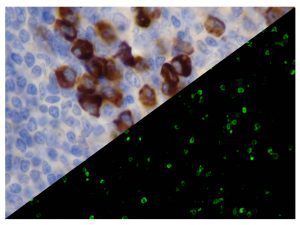

It is the ICU physician who is most likely to witness one of the deadliest manifestations of the abnormal immunological response, the cytokine storm syndrome (CSS). This response is also referred to by some as the cytokine release syndrome (CRS). CSS is characterized by continuous activation and expansion of macrophage and lymphocyte populations, which secrete large amounts of cytokines, causing the cytokine storm. This massive cytokine release is akin to hemophagocytic lymphohistiocytosis (HLH) disease, a syndrome characterized by initial unchecked and persistent activation of cytotoxic T lymphocytes and NK cells.

Clinical and laboratory manifestations of HLH include fever, enlarged liver and/or spleen, neurologic dysfunction, coagulopathy, liver dysfunction, cytopenias (i.e., low levels of erythrocytes, leukocytes, and/or platelets), hypertriglyceridemia, hyperferritinemia, hemophagocytosis, and eventually diminished NK cell activity as the immune system becomes progressively paralyzed. HLH can be familial (primary HLH) or secondary to another disease process (sHLH), such as rheumatic disease, in which it is referred to as macrophage activation syndrome (MAS, characterized by elevated ferritin).